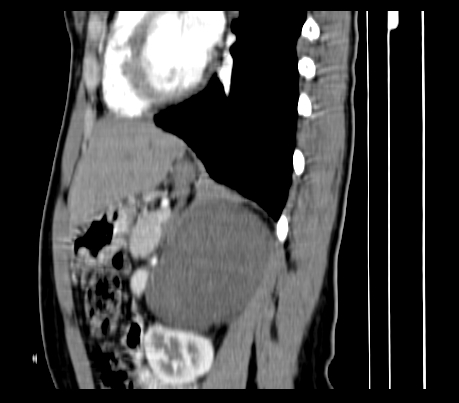

标题: CT23915:女 20岁 全身长疙瘩三年 今日多体位查 看看吧 [打印本页]

标题: CT23915:女 20岁 全身长疙瘩三年 今日多体位查 看看吧

动脉期